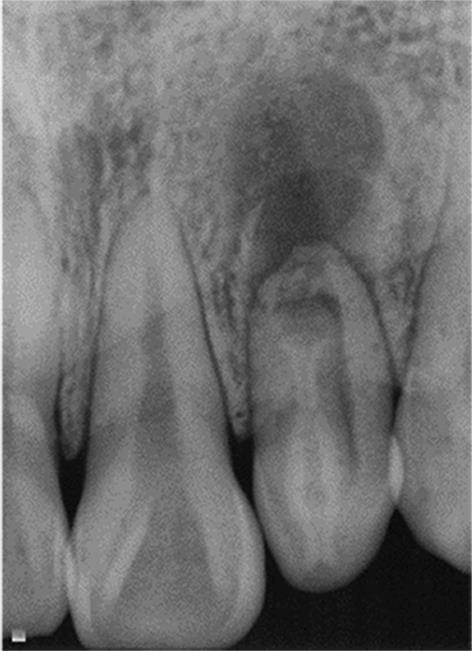

• 显微根尖手术治疗上颌侧切牙Oehlers Ⅲ型牙内陷1例

2024, 49(1):101-104. DOI: 10.13406/j.cnki.cyxb.003375

摘要 (34) HTML (13) PDF 9.96 M (122) 评论 (0) 收藏

摘要: